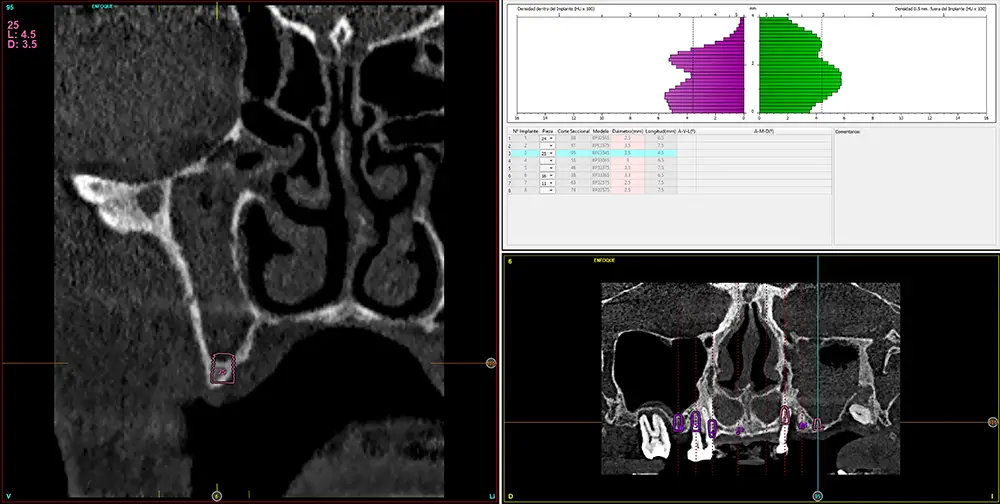

Para realizar una planificación precisa del caso y determinar el volumen óseo residual antes de la cirugía implantológica, se realiza un estudio mediante tomografía de haz cónico (cone-beam) y se visualiza mediante un software específico (BTI-Scan IV). Esta exploración permite medir con exactitud la altura y anchura de la cresta ósea, así como evaluar la densidad de las zonas en las que se prevé colocar los implantes, facilitando así una planificación quirúrgica fiable y ajustada a las necesidades anatómicas del paciente44–47. En las imágenes del cone-beam de control, observamos en el segundo cuadrante una atrofia vertical extrema, con zonas de menos de 4 mm de altura, donde se planifican implantes de 4,5 mm de longitud que serán colocados mediante el procedimiento de elevación transcrestal con fresa de corte frontal y con hueso autólogo obtenido del fresado embebido en PRGF-Endoret como material de injerto. Esta técnica, descrita por nuestro grupo de estudio, nos permite realizar un abordaje seguro del seno maxilar con una escasa invasividad (figs. 8-10)9,25,29,36.

Figs. 9-10. Medida de la zona con mayor atrofia del segundo cuadrante menor a 4 mm de altura y planificación del implante de 4,5 mm de longitud que será colocado mediante el procedimiento de elevación transcrestal anteriormente descrito.